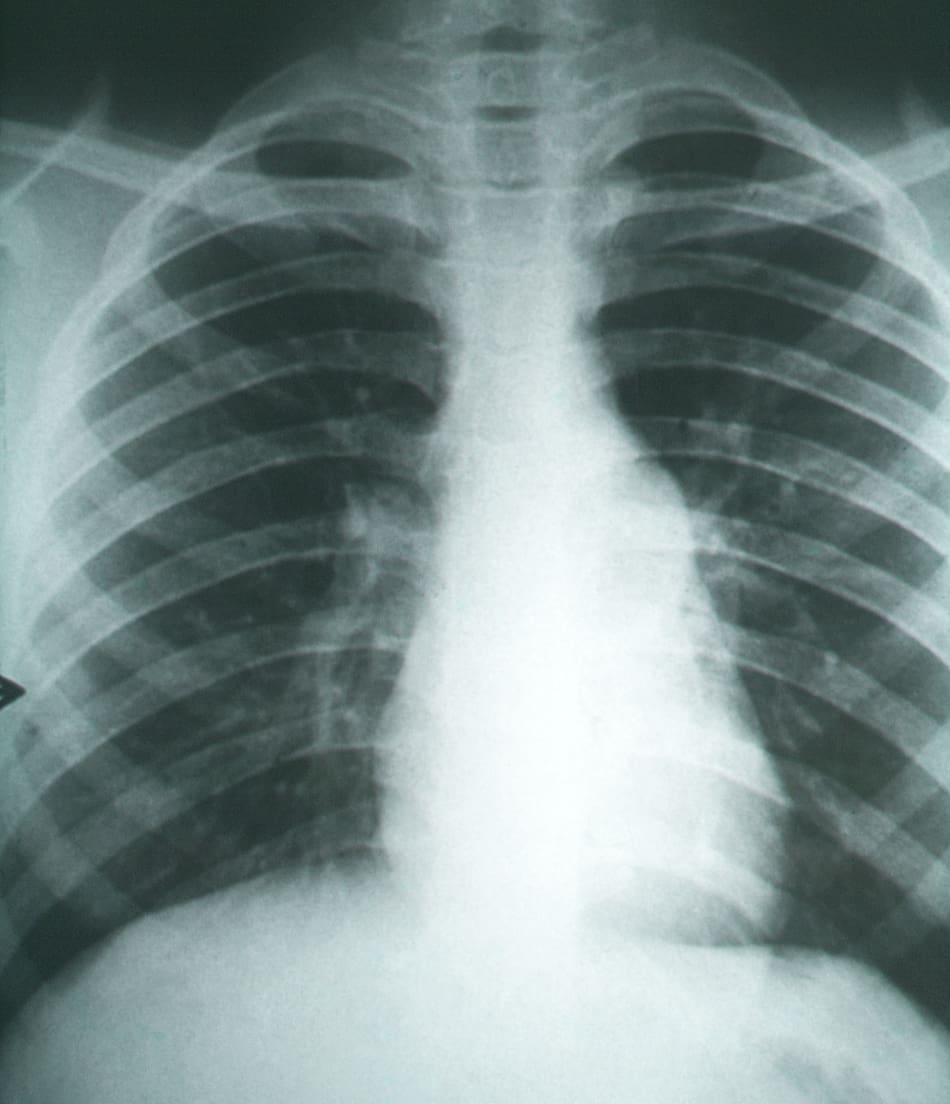

En Argentina, más de la mitad de los casos diagnosticados corresponden a formas crónicas pulmonares o diseminadas, lo que indica una falta de detección temprana de la enfermedad.

Fibrosis pulmonar secundarias a la coccidioidomicosis.. Foto: Wikipedia.